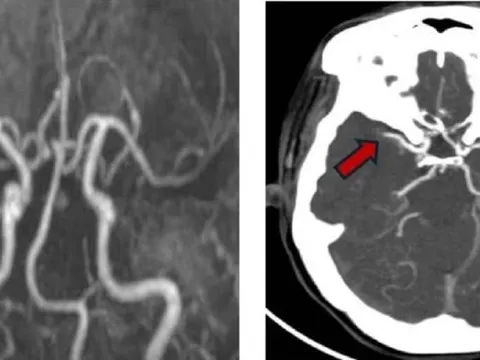

Người phụ nữ liên tiếp bị 2 cơn đột quỵ

TPO - Tưởng như đã vượt qua cơn nguy hiểm sau lần đột quỵ đầu tiên, người phụ nữ 57 tuổi không ngờ lại đối mặt tiếp cơn đột quỵ thứ hai trong vòng chưa đầy 24 giờ.

Đà Nẵng: Bé 13 tuổi đột quỵ khi đang tập văn nghệ

TPO - Ngày 16/6, Bệnh viện Đà Nẵng cho hay vừa phẫu thuật thành công, cứu sống một bệnh nhi 13 tuổi bị xuất huyết não nghiêm trọng do vỡ dị dạng mạch máu não - một trong những nguyên nhân đột quỵ thường bị bỏ sót ở trẻ em.